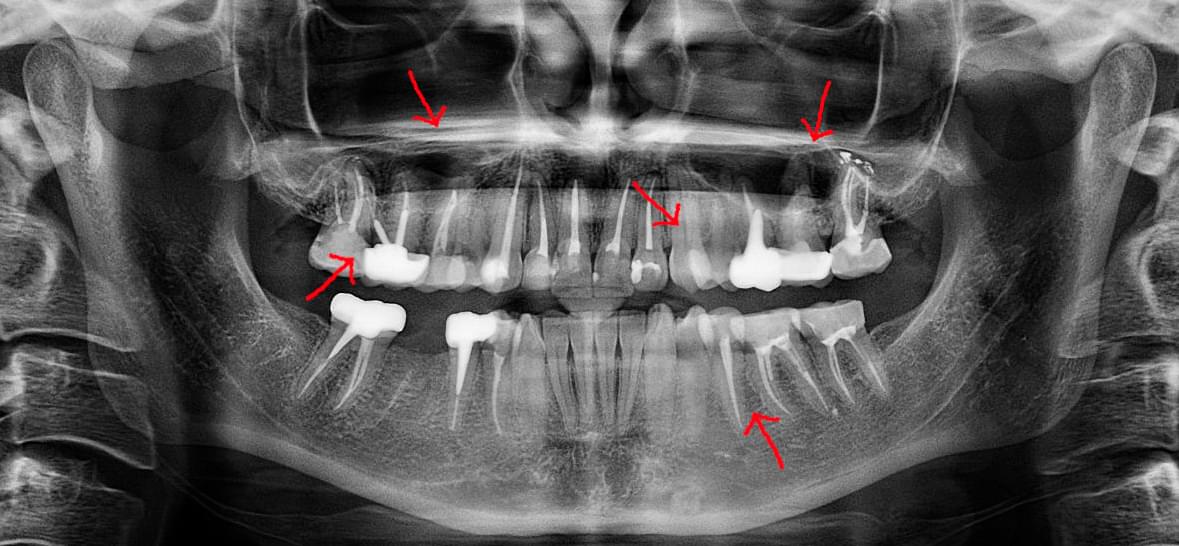

Головний недолік 2D-рентгену — це площинне зображення. Зуби, корені, щільна кістка та гайморові пазухи накладаються один на одного, створюючи «візуальний шум».

Коли коріння «ховає сюрпризи» - Корені зубів часто мають складну кривизну, гачкоподібні закручення або розгалуження, які на звичайному 2D-знімку накладаються один на одного, створюючи ілюзію прямого каналу. На плоскій картинці неможливо побачити реальний об'єм та напрямок вигину, що критично важливо при видаленні «зубів мудрості» або ендодонтичному лікуванні. КТ MyRay дає змогу лікарю заздалегідь побачити 3D-геометрію кожного кореня, оцінити його близькість до нижньощелепного нерва чи гайморової пазухи та підібрати правильну тактику роботи. Це мінімізує ризики поломки інструменту в каналі або травмування сусідніх структур, перетворюючи складну хірургію на прогнозовану процедуру.